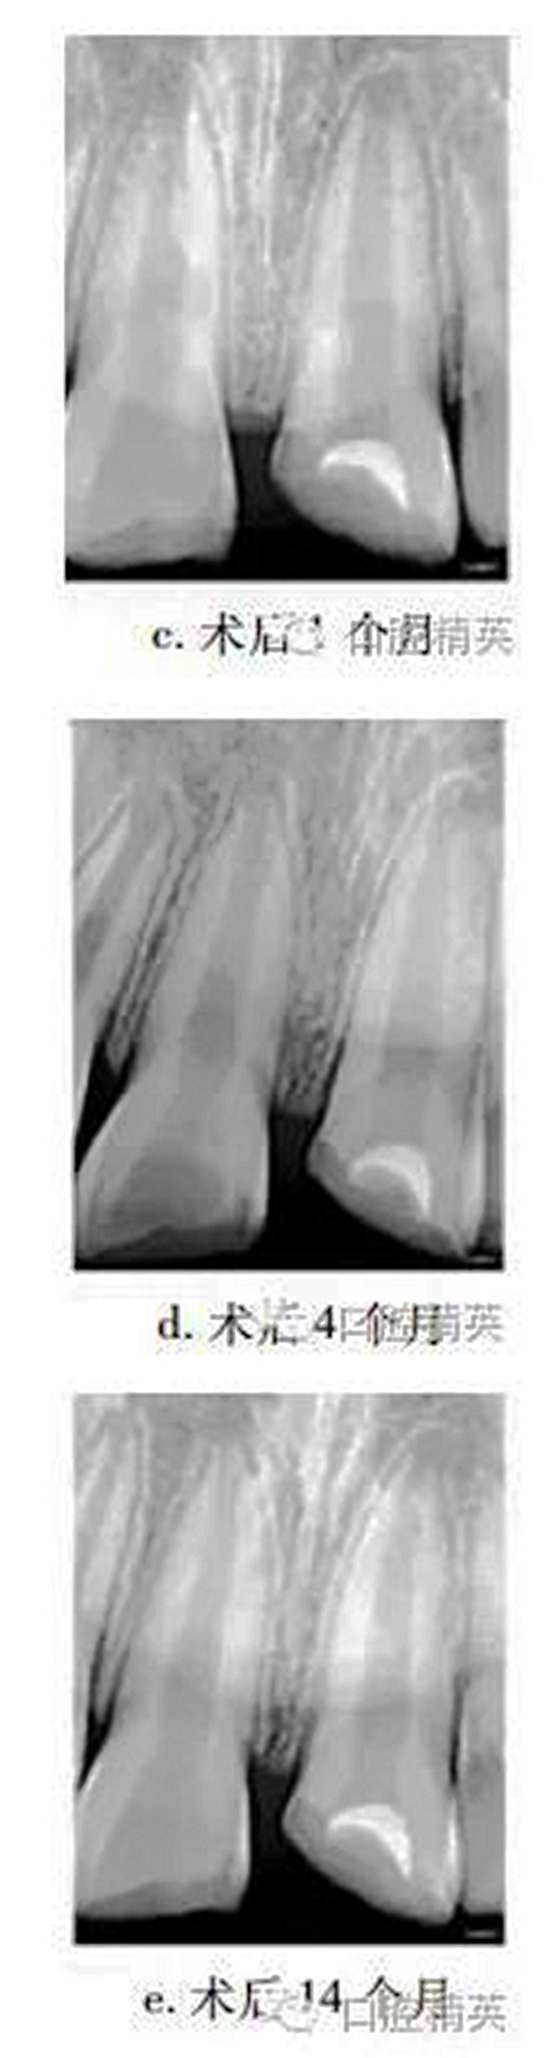

1個(gè)月后復(fù)查,21無(wú)明顯不適,上唇腫脹減輕,患牙冷熱診(-),牙髓電活力測(cè)試(-),X線片示根尖無(wú)明顯變化(圖c)。4個(gè)月后復(fù)查,患牙無(wú)明顯不適,冷熱診(±),牙髓活力測(cè)試(-),X線片示患牙根管腔略見(jiàn)縮窄(圖d)。14個(gè)月后復(fù)查,患牙無(wú)明顯不適,牙髓活力測(cè)試(+),但較正常對(duì)照牙低;X線片示:蓋髓劑下方可見(jiàn)斷斷續(xù)續(xù)的高密度影像,根管壁增厚,管腔明顯縮窄,根尖孔聚攏傾向,牙根長(zhǎng)度較初診時(shí)增加(圖e)?;佳涝涮钗锫杂腥睋p,稍加預(yù)備后玻璃離子暫時(shí)恢復(fù)牙冠形態(tài)。